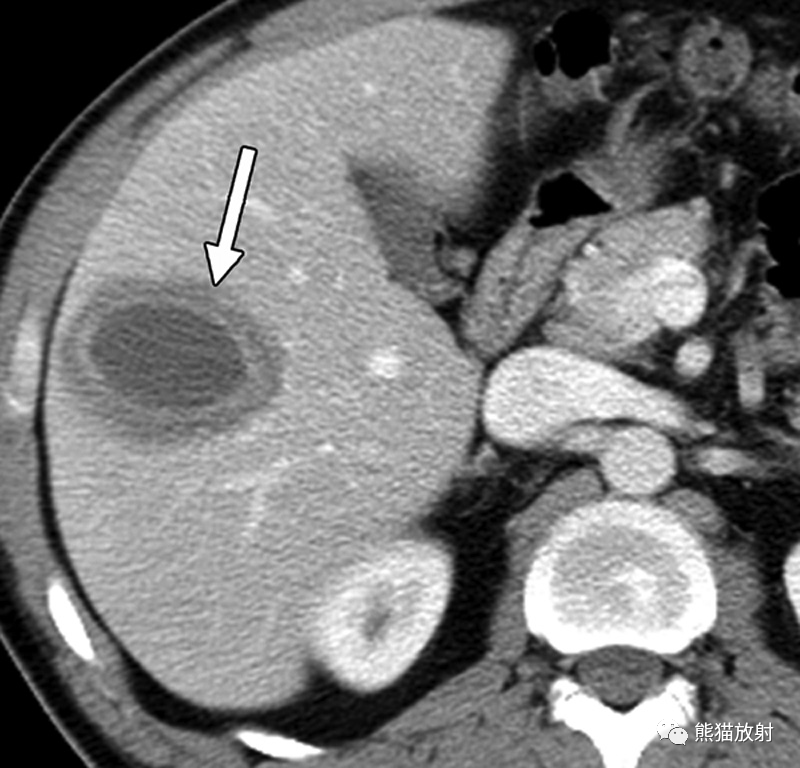

播散性念珠菌病,中性粒细胞减少症患者在造血干细胞移植后34天出现发热。(a)脂肪抑制T2WI图像显示肝内散在多发小的中等高信号结节(箭头)。(b) DWI (b=800s/mm2) 显示真菌病灶扩散受限呈高信号(箭)。(c) 脂肪抑制T1WI仅显示一些较大结节,呈低信号(箭头)。(d) 对比增强动脉期脂肪抑制T1WI图像显示多发边界不清的明显强化肝结节(箭)。动脉期CT或MR图像可在早期描述更多的病灶,尤其是在病灶中央坏死出现之前。